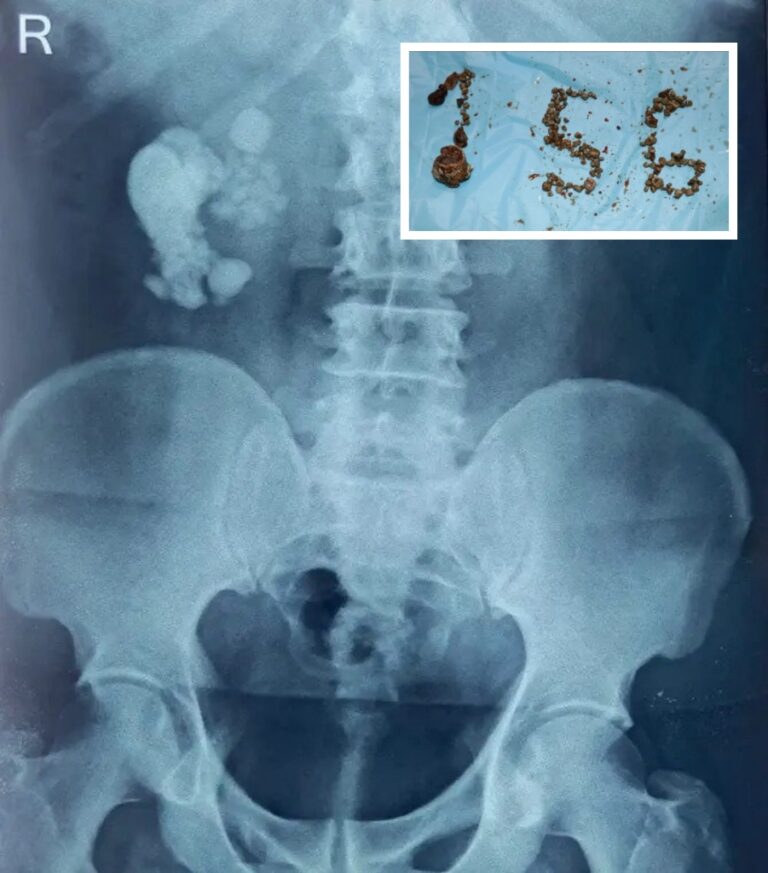

156 batu karang